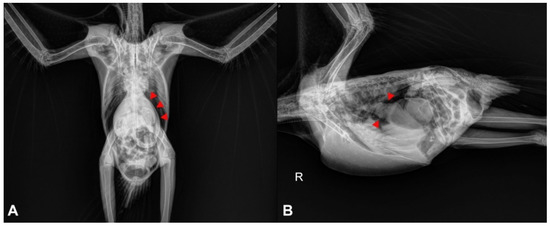

In cases of suspected gastrointestinal disorders related to PDD, diagnostic imaging may be a useful resource for the clinician. The most cost-effective imaging tools are usually survey and contrast radiographs, which are often readily available for clinical veterinarians (Figure 2). These techniques can provide relevant information about the size and motility of the gastrointestinal compartments, especially the proventriculus [20].

Figure 2. Radiographic projections of a young macaw with PDD. (A) Ventrodorsal projection. Moderate dilatation of the proventriculus (arrowheads). The proventriculus extends beyond the liver edge. (B) Lateral projection. The proventriculus (arrowheads) is moderately distended and contains ingesta and gas. R = Right side.

It has been suggested that proventricular diameter-to-keel height ratio obtained from lateral radiographic projections is a valuable method for identification of an enlarged proventriculus, and ratio values above 0.52 indicate proventricular dilatation [21]. It is important to note that PDD is not the only disease that can cause proventricular dilatation in psittacine birds, and other causes such as foreign bodies, neoplasia, lead toxicity and Macrorhabdus ornithogaster infection should be ruled out.

In healthy psittacine birds, contrast media such as barium sulfate should be visualized by radiographs reaching the cloaca between 90 min to 3 h after its administration by gavage [22]. Therefore, contrast radiographs may be useful to identify alterations in the gastrointestinal transit time, and it has been observed that PDD-affected birds may have an increased transit time [20].